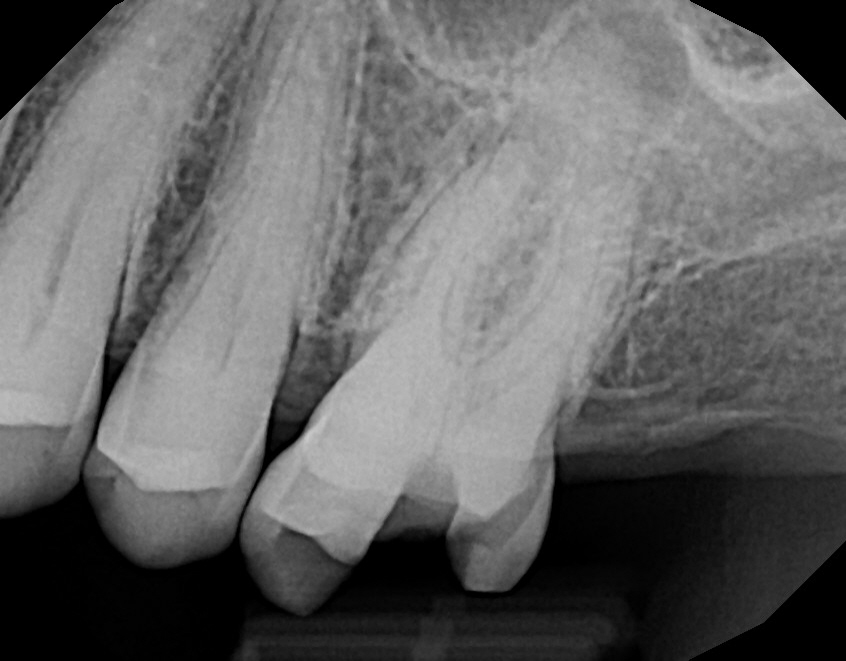

Case 3

The left images shows that the molar has one root shorter than the other--this is not how this tooth started out. This case shows that even the root of a tooth can be eroded away by a tooth infection, just like the bone, when an infection is present. The infection extended all around the back root--the dark areas around the tooth are infection-related bone loss. The front root had an infection just at the root tip. The right images shows complete healing.